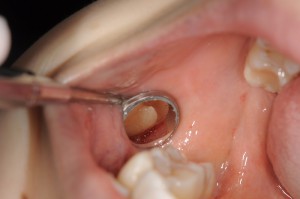

下の写真の患者さんは、「親知らずが生えてきて、知らないうちにその手前の歯が虫歯になった」ケースです(虫歯を取り除いた後の写真です)。

このようなケースは結構多く認められますが、しっかり治療するのはかなり難易度が高くなることが多いと思います。

というのも、奥歯の裏の虫歯なので、患者さん自身も見えませんし、術者の歯科医師であっても正面からは全く見えません。

奥歯の裏を見るためには、鏡に反射して映る像を見ながら治療する「ミラーテクニック」を応用しますが、虫歯を削る際や、充填(詰める)する際にミラーテクニックを応用するのは至難の業でもあります。また、奥歯の周囲には頬粘膜や筋肉があるため、通常のミラーでは見るのが精いっぱいで、治療中はミラーが入らない事も少なくありません。

そのな時には、通常のミラーよりも小さい12mmのミラーを使用しています。

しかし、その分術野が狭くなるため、拡大ツールが必要になります。(マイクロスコープや強拡大ルーペ)